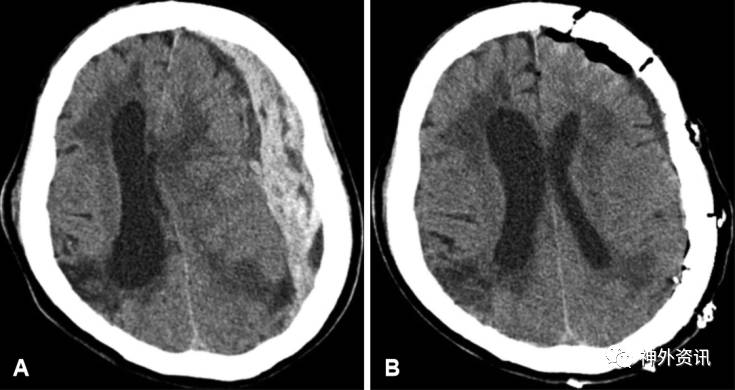

46例ASDH患者中,20例(43%)采用开颅手术,即CO组(图2);26例(53%)行去骨瓣减压术,DC组(图3)。DC组患者与CO组相比,术前GCS评分低,瞳孔无光反应者多,CT显示蛛网膜下腔出血发生率高。因此,DC组患者的病情明显比CO组严重(p=0.017)(表2)。术后随访6个月时,两组患者的改良Rankin量表评分提示,CO组患者的预后明显优于DC组(p=0.004)。

图1. 急性硬脑膜下血肿开颅手术术前(A)与术后(B)的CT扫描。